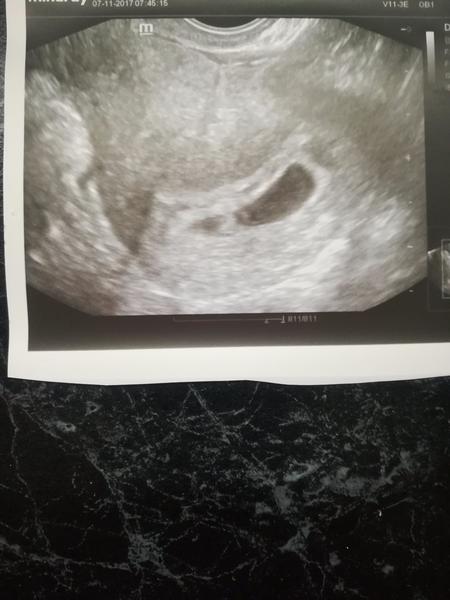

V 7tt jen gestační váček

Kdo s tím má zkušenosti.. je pravděpodobné, že když v 7tt+0 byl vidět JEN gestační váček s mini mini tečkou vevnitř, že se to ještě v dobré obrátí? Jasné, doktor to počítá podle poslední MS, prostě na mě vytáhl tabulku s tím, že teda v tento den má mít tolik a tolik mm a když nemá, tak okamžitě zamlklé těhotenství a všechno špatně. V papírech rovnou zapsané: missed AB. Taky jsem na UTZ viděla to nic...jen černý gestační váček a nějakou mini tečku, která by měla mít 8 mm a srdíčko.. Jen se prostě nechci nechat natlačit do revize. Takže mám přijít za týden, na 8+0, což mi bylo řečeno s tragickým obličejem. Těšila jsem se na vytištěný obrázek, a mám akorát uřvaný obličej.

@evorka jestli jsi měla ovu 4.10. Tak jsi to měla stejně jako já. Na gynde jsem pak byla 7.11 a byla jsem podle UZ teprve 6+3tt. Takže to vychází. Kolikrát tady holky píšou že ještě neměli srdíčko a tak různě. Posílám ti mé foto jak to vypadalo u mě už tedy i se srdíčkem. Ale doufám že u tebe bude vše ok a prcek vyroste.